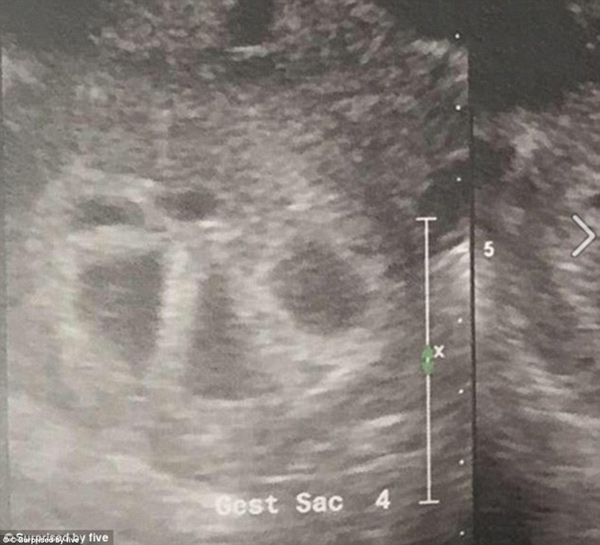

When she asked to use another sonogram machine so she could have a clearer view of the babies, her world was turned upside-down when the doctor found five separate heart beats.

Mrs Tucci asked to take a second sonogram to see her babies better and doctors were shocked to find out that instead of two heartbeats, there were five.

'My legs start [sic] to shake uncontrollably and all I can do is laugh.. The sonographer then told me the term for 5 is QUINTUPLETS!!' she continued.

'I called my husband from the ultrasound room but I don't think he believed me at first. He quickly drove down. I could see the excitement in his face he told me " We can do this".'